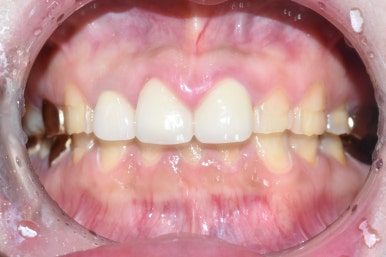

자연적으로 부식되어 있는 치아

멀쩡한 치아에다가 보철물을 하면

아주아주 미용심미적인 이유(성형처럼) 외에는

딱히 보철물을 붙이지 않는데,

이 환자분의 경우 이미 크라운도 되어있는 상태이고

치아들도 많이 부식되어 있어 이미 자연적으로 손상이 많이 되어있는 치아이므로

오히려 라미네이트나 크라운 같은 보철물을 하는 것이

보이는 것에서나 치아를 유지하는 측면에서 좋다고 판단되었습니다.